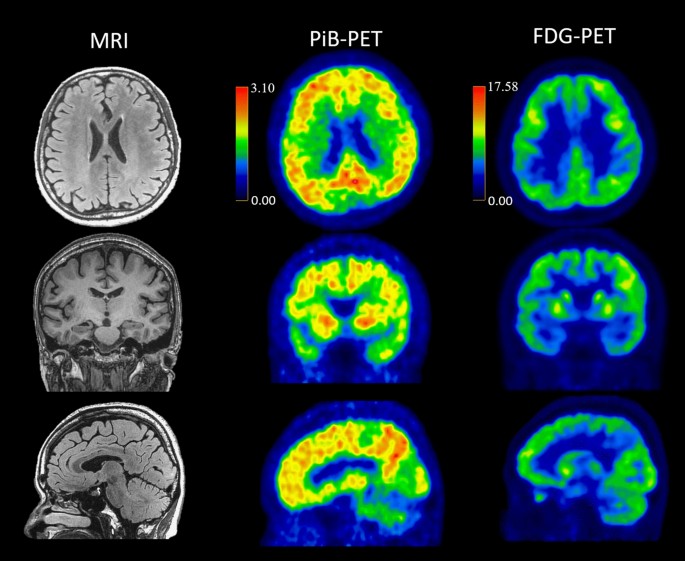

PSEN1 c.392A > G, p.His131Arg was discovered in a female patient who had impaired memory and topographic disorientation since age 49. Pittsburgh compound B positron emission tomography (PiB-PET) amyloid imaging of this patient demonstrated extensive cortical and striatal amyloid deposition (Fig. 2). Her elderly sister had amnesia at age 52, and her father died prematurely at age 65, supporting the autosomal dominant inheritance pattern.

Brain imaging of a patient with PSEN1 p.His131Arg and age at onset of 49 years. Brain MRI at age 61 and PiB-PET and FDG-PET at age 62 were showed. MRI showed mild medial temporal atrophy, mild parietal atrophy and minimal white matter hyperintensity; PiB-PET demonstrated extensive cortical and striatal amyloid deposition; FDG-PET showed decreased uptake in precuneus and bilateral temporo-parietal region.

The PSEN1 p.His131Arg mutation was first reported as a variance of unknown significance by Ikeda et al. in 201339, where a Japanese female patient had amnesia onset at age 45 with a negative family history. This variant was absent from the variant databases. In silico analyses predicted the p.His131Arg substitution to be benign by Polyphen-2, but damaging by SIFT. Using this mutant, Aβ42/Aβ40 ratio was slightly increased in an in vitro assay but in mouse neuroblastoma cells, there was an approximately twofold increase40. Therefore, the researcher described the originally variance of unknown significance to be likely pathogenic in 2020. With the positive PiB-PET of our patient, solid clinical evidence was added to PSEN1 p.His131Arg.